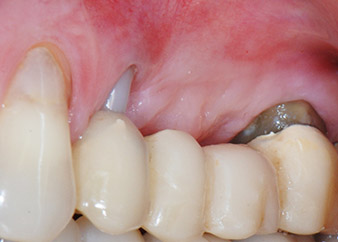

Risultati intermedi dopo due mesi

Le figure 17 e 18 mostrano il risultato clinico due mesi dopo l'intervento chirurgico. Il dente 24 mostra mobilità ridotta di classe 1 secondo Miller e i tessuti molli sono privi di infiammazione. A questo punto l'utilizzo della sonda è stato evitato per impedire una nuova infezione e per non disturbare l'attacco epiteliale. Era stata programmata una visita di controllo al rientro e il posizionamento dei perni di guarigione sei mesi dopo l'inserimento degli impianti.

Durante la visita prevista due mesi dopo l'intervento chirurgico, la mobilità del restante "elemento dentale" 24 si era già ridotta dalla classe 2 secondo Miller alla classe 1. L'attacco del tessuto molle era a livello del vicino dente 23. Inoltre, la paziente non presentava sintomi endodontici o periodontali, quindi la prognosi è stata rivista.

Tuttavia, poiché la maggior parte del tessuto osseo buccale e prossimale è mancante e il materiale composito di ricostruzione si estende fino alla sezione apicale della radice, per ragioni biologiche non è possibile attendersi un livello di riattacco più elevato (Sculean et al., 2008).